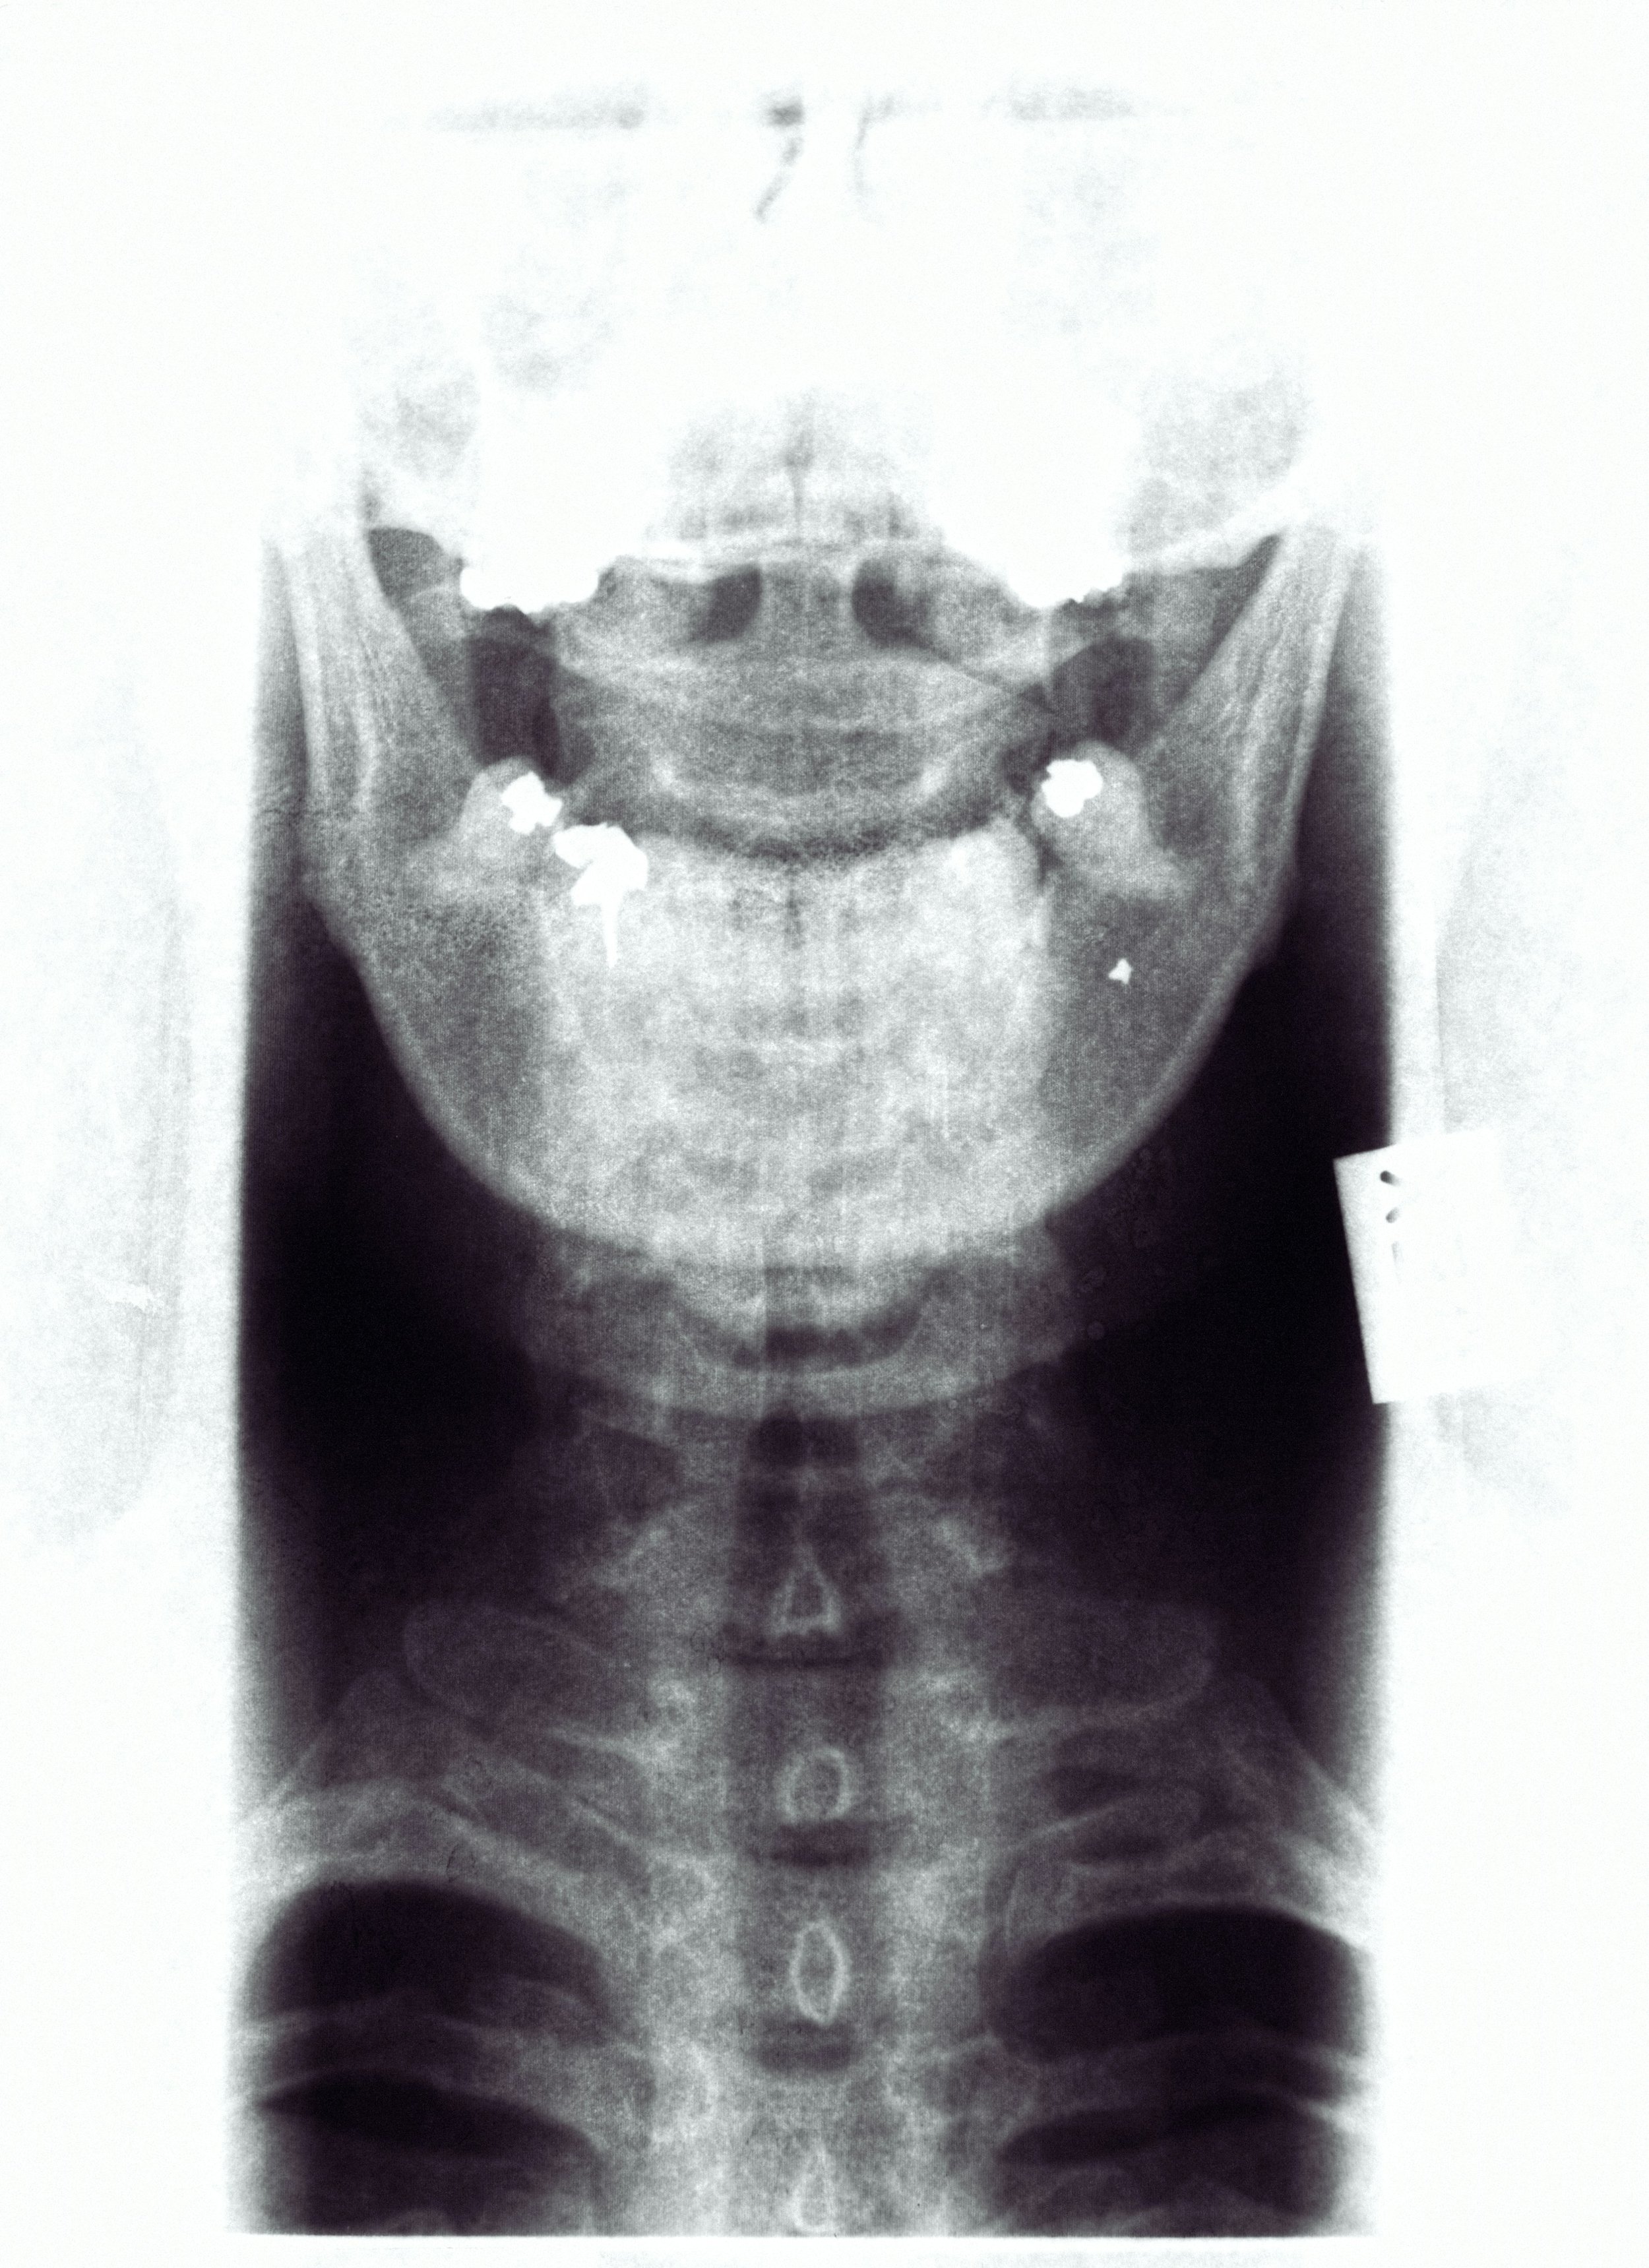

Minimally Invasive Anterior Cervical Spine Discectomy and Fusion

This is a surgical procedure performed on the cervical spine (neck) from the front. The surgeon makes a small incision in the front of the neck, typically in the natural skin folds, to minimize scarring. The muscles, blood vessels, and other soft tissues are gently moved aside to expose the cervical spine. A damaged or herniated disc is removed, all or part. The surgeon may then insert a bone graft (from the patient, a donor, or synthetic material) between the vertebrae to encourage them to fuse, stabilizing the spine. Depending on the procedure, screws, plates, or other hardware may be used to stabilize the spine during the healing process.

-

This procedure can be done for cervical disc herniation, cervical spondylosis (DDD), spinal stenosis, fractures or dislocations, and tumors.

This provides relief of nerve compression, which can alleviate pain, weakness, or numbness in the neck, shoulder, arms, or hands. Spinal alignment and function is improved, leading to improved quality of life. The risk of permanent nerve damage or disability is also reduced.

Surgery is typically done as an outpatient. A cervical collar or brace may be used for several weeks to support the neck during healing. PT is often recommended to restore the range of motion and strength. Full recovery can take several months, although many patients experience significant symptom relief within weeks.

Posterior Cervical Fusion

procedure performed from the back (posterior) of the neck to relieve pressure on the spinal cord and or nerve root or to stabilize the cervical spine. It can involve removing bone or soft tissue (Laminectomy – removal of the lamina, the roof of the vertebra) to enlarge the canal, or Foraminotomy – enlarging the foramen where nerves exit. Posterior cervical decompression and fusion is the most common (PCDF or PCF). If fusion is required, it involves screws and rods for stability, and a bone graft or bone graft substitute to promote fusion.

When conservative treatments have failed or when there is progression of neurologic symptoms, cervical fusion can be done for cervical spinal stenosis, cervical radiculopathy, cervical instability, cervical tumors, and infections that require decompression and stabilization, and also for multilevel degenerative disc disease when several levels are affected, making an anterior approach less effective.

The possible benefits include the relief of the symptoms caused by spinal cord and nerve compression, such as neck and arm pain, decreased hand coordination, balance, and strength, as well as stopping further neurologic decline. Also improved stability in cases of spinal instability and deformity, and better overall function and quality of life.

Typically, this requires a 1-3 day hospitalization, depending on the number of cervical levels addressed. Initial recovery, the first few weeks, there is pain and stiffness, which are controlled with medications. A neck brace may be worn for several weeks to support healing. Walking and light activity are encouraged early. Heavy lifting should be avoided, as well as overhead reaching and sudden neck movements. During the intermediate recovery period, 6-12 weeks, a gradual increase in activity and physical therapy starts. Desk work is permitted at 2-4 weeks, and physical jobs take 3-6 months. The full bone fusion takes between 3 months to one year, and most patients have lasting pain and functional improvements, particularly if surgery is completed before significant nerve or spinal cord damage occurs.